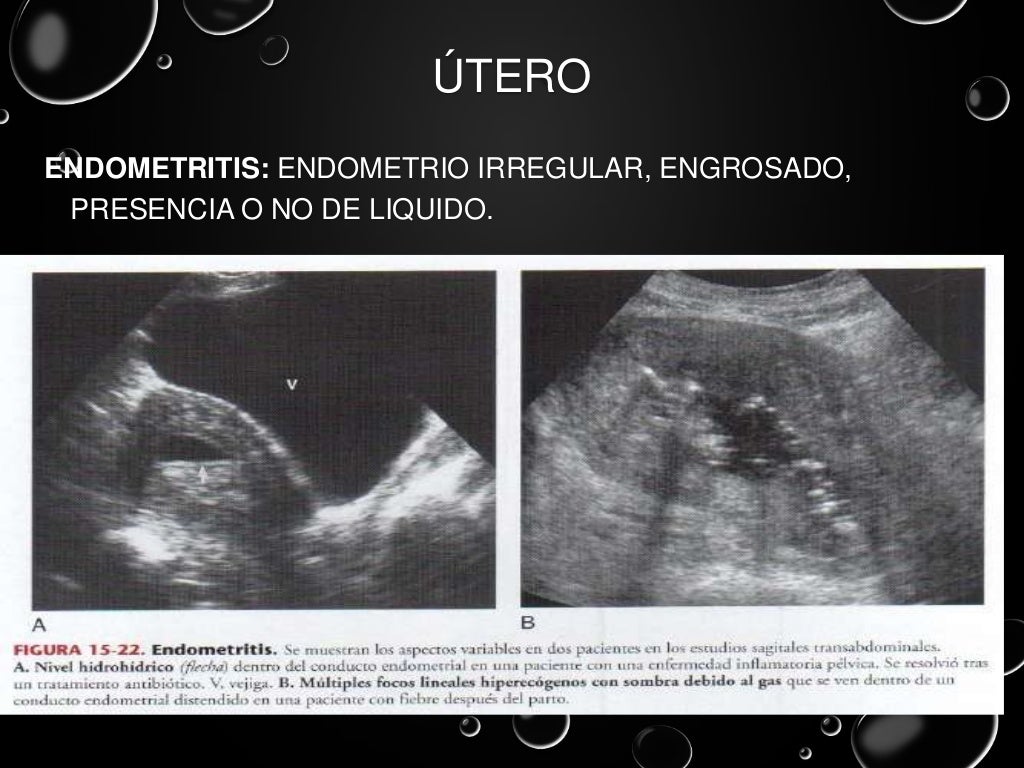

ultrasonido pelvico salud digna El precio del ultrasonido pélvico en salud digna laboratorios puede variar ya que hay varios tipos de ultrasonido que componen la zona pélvica. Ultrasonido de abdomen con un costo de $105. Las imágenes ecográficas del ultrasonido pélvico pueden también ayudar a determinar posibles quistes ováricos o fibromas uterinos, así como cáncer ovárico o uterino. Un ultrasonido o ecografía es un procedimiento seguro que utiliza ondas de sonido no audibles para el ser humano, las cuales escanean diferentes partes del cuerpo, con el propósito de crear una imagen del interior. El ultrasonido pélvico es primordial para diagnosticar el origen del dolor pélvico, sangrado anormal, u otros problemas menstruales. En un ultrasonido obstétrico, se explora tu abdomen y cavidad pélvica durante el embarazo, con lo que es posible. Un ultrasonido intravaginal también puede ayudar a diagnosticar problemas de fertilidad en la vejiga, los riñones y la cavidad pélvica. Ultrasonido 4d con un costo de $230.

Ultrasonido pelvico

Source: es.slideshare.net